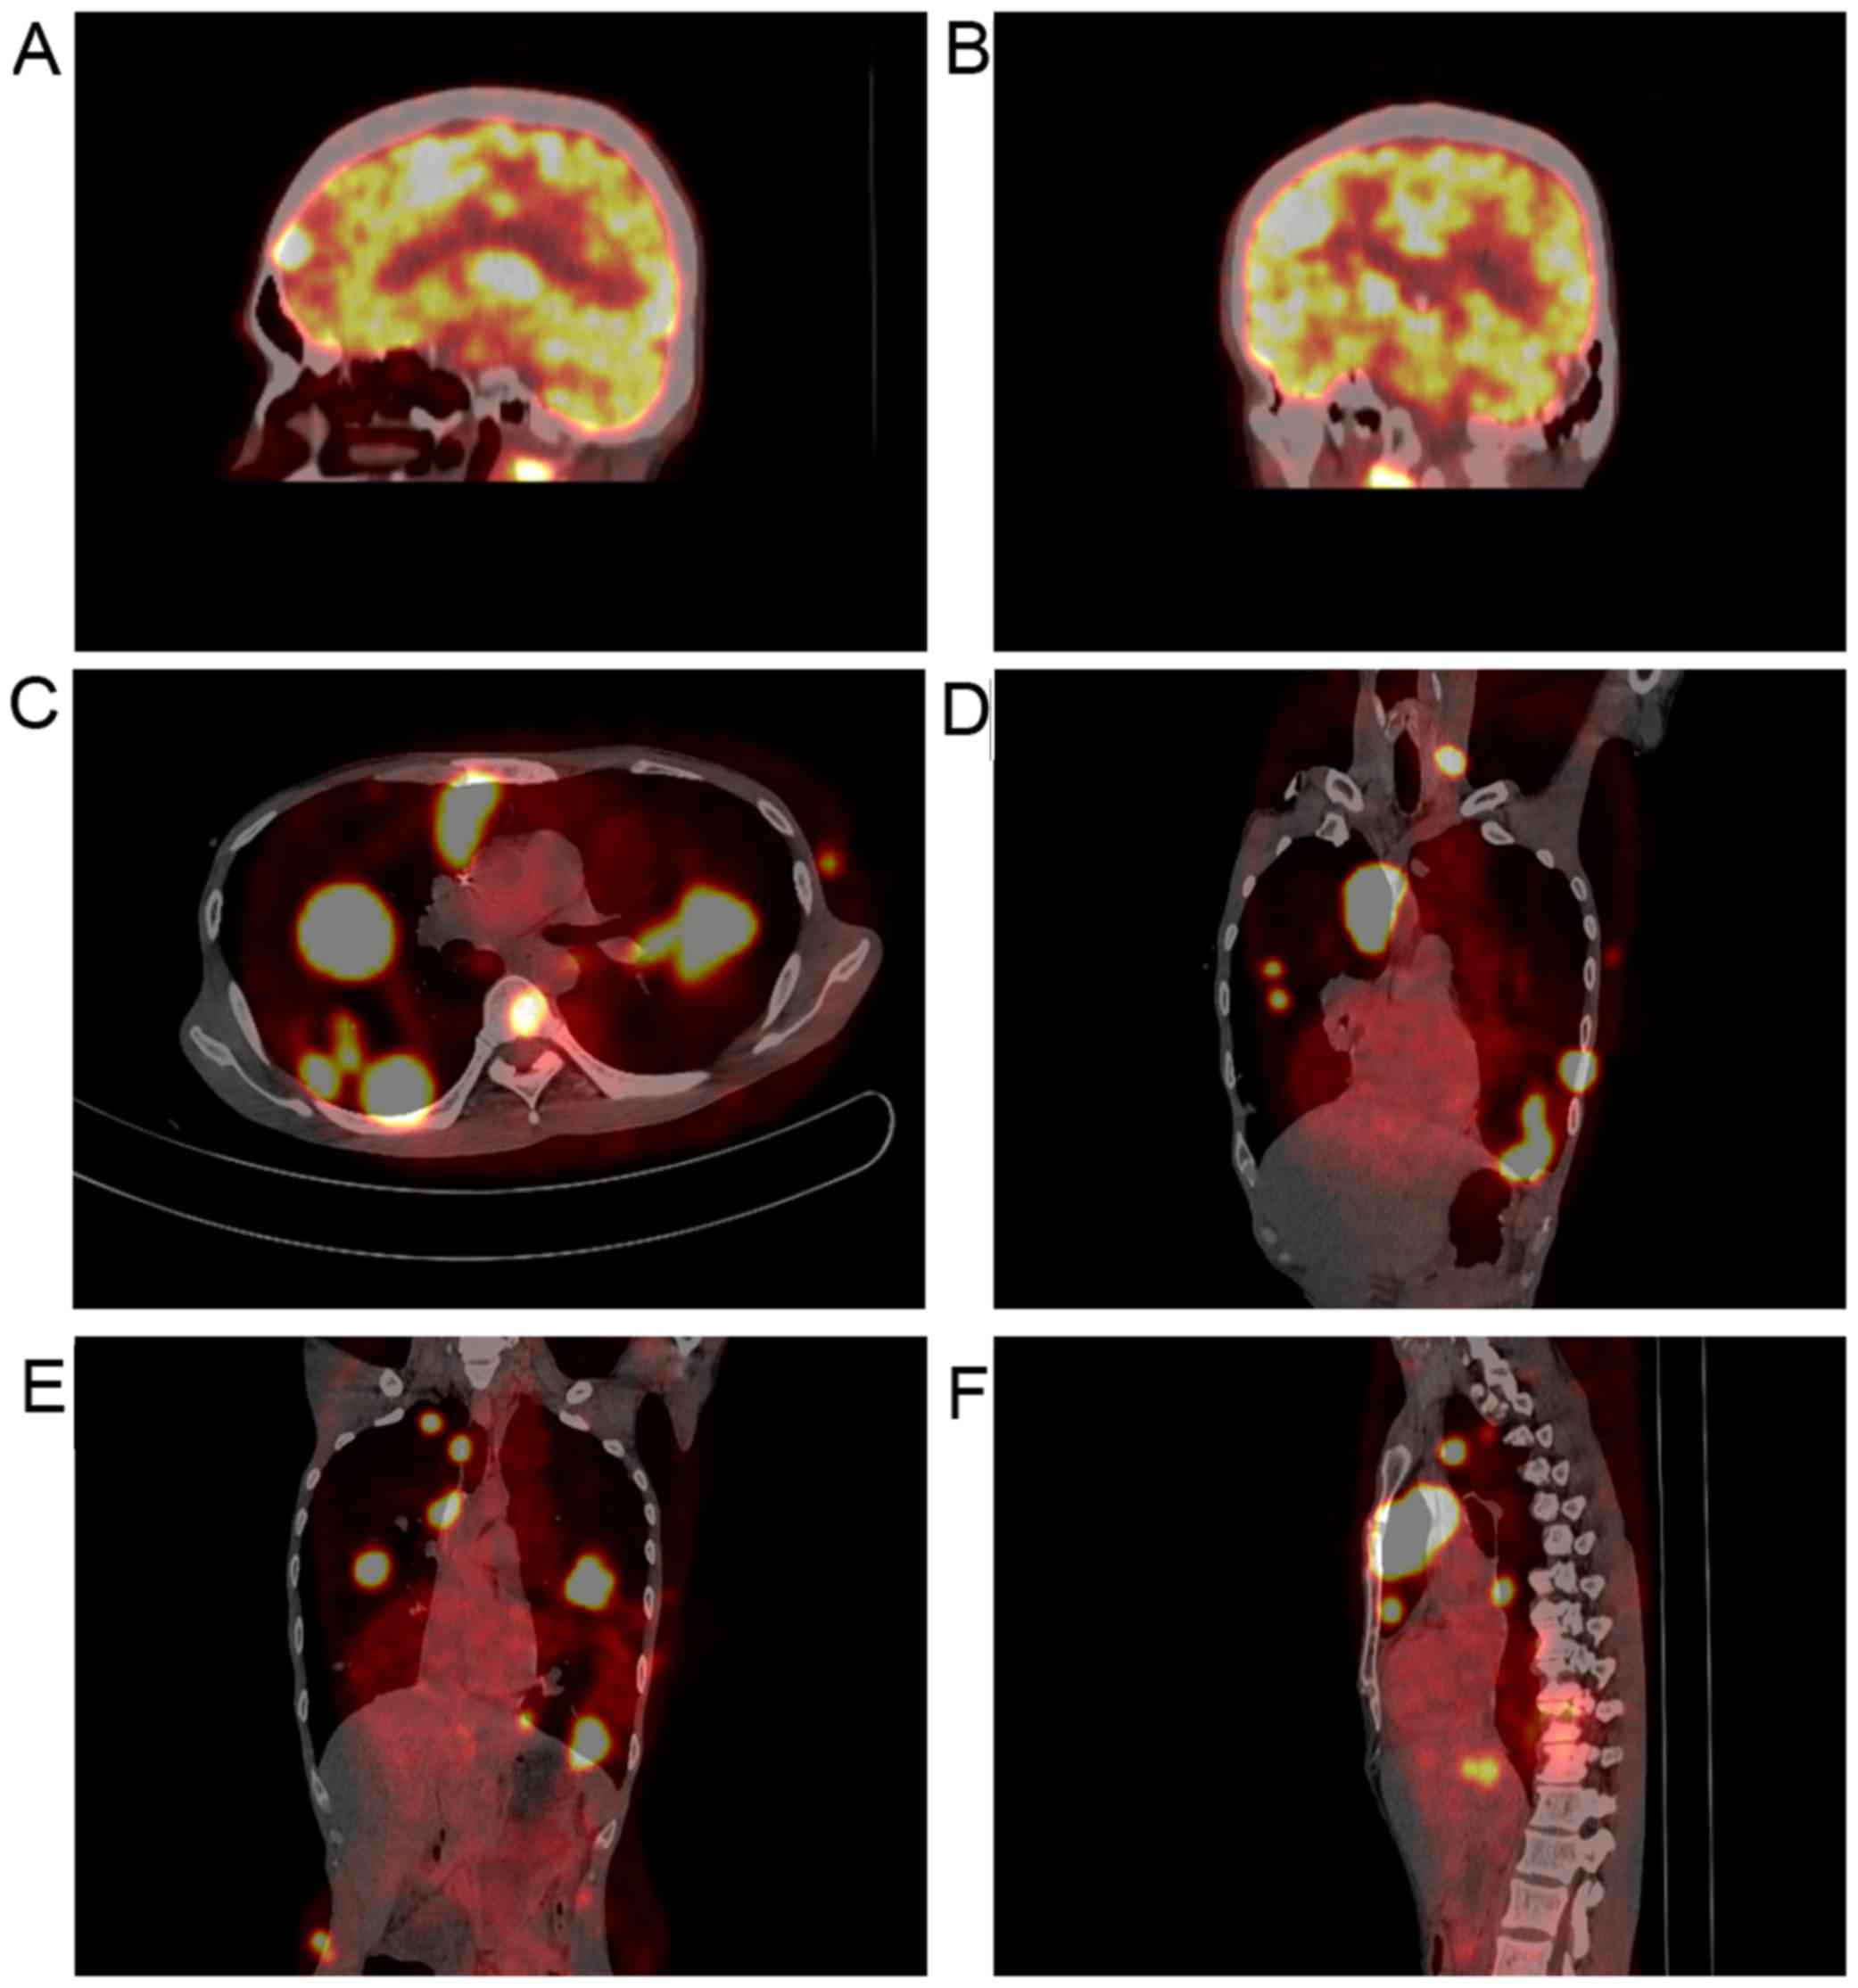

A 42-year-old man presented with a 2-week history of dry cough and thoracalgia accompanied by intermittent mild fever and headaches; however, no night sweats or weight loss were reported. The patient had a history of sexual contact with men. A total of 18 months prior to the presentation, the patient was diagnosed with pulmonary tuberculosis (TB) in a specialized hospital in China following the development of fever and cough. The results of acid-fast staining on sputum smear analysis and a chest X-ray showing infiltrates in both lungs were consistent with typical TB manifestations (Fig. 1A). Simultaneously, the patient was diagnosed with human immunodeficiency virus (HIV) infection. According to the guideline for adult HIV/AIDS patients with opportunistic infections recommended by the Center for Disease Control and Prevention, Infectious Diseases Society of America and National Institutes of Health (http://aidsinfo.nih.gov/guidelines), the specialist consultant at the TB specialized hospital empirically prescribed first-line anti-TB treatment for this patient with 2 months of isoniazid, rifampicin, ethambutol and pyrazinamide, followed by 4 months of isoniazid and rifampicin. As a result, the fever and cough were eliminated, and the pulmonary infiltrate was also absorbed (Fig. 1B and C). Thus, according to the guideline, further testing for anti-TB drug sensitivity was not deemed necessary. One month after the aforementioned treatments, lamivudine, tenofovir and efavirenz were administered to the patient as an additional anti-HIV treatment strategy; however, the medication was not taken regularly and follow-up appointments were also irregular. A physical examination was performed following admittance to the hospital, which revealed bilateral oral leukoplakia and tenderness in the left lower chest. Sputum acid-fast staining analysis did not reveal any signs of TB infection, and no anaerobic bacteria, aerobic bacteria, fungi or Mycobacterium tuberculosis were present in blood culture. The results of the laboratory tests performed on admission are presented in Table I. Lumbar puncture was performed due to the patient suffering from headaches; however, no pathogens were found in the cerebrospinal fluid (CSF). The results of CSF examinations are presented in Table I. A chest X-ray revealed multiple masses in both lungs (Fig. 1D) and a subsequent thoracic computerized tomography (CT) scan confirmed this result (Fig. 1E-J). Brain magnetic resonance imaging (MRI) revealed nodules in the left frontal cortex and the bilateral basal ganglia. (Fig. 1K and L). The patient was initially suspected to be suffering from a pulmonary and CNS infection; however, the X-ray and laboratory findings did not support this suspected diagnosis. To determine the composition of the lung and brain masses, a percutaneous lung needle biopsy was performed, revealing large numbers of lymphocytes ranging in size from medium to large, with oval or round nuclei containing fine chromatin and scanty cytoplasm (Fig. 2A-C). Furthermore, immunohistochemistry staining analysis revealed that these results were consistent with a diagnosis of germinal center B-cell-like (GCB) DLBCL (Fig. 2D-G). 18F-labelled fluorodeoxyglucose (FDG) positron emission tomography (PET) revealed that FDG uptake was high in the brain, mediastinum, lungs, right adrenal gland, thoracic vertebrae and ribs (Fig. 3). Based on these results, experienced radiologists suggested a diagnosis of systemic lymphoma with CNS involvement. Then, bone marrow aspiration was performed, and cytological examination revealed normal bone marrow hyperplasia, without the presence of lymphosarcoma cells. Therefore, the patient was diagnosed with stage IV NHL according to the Ann Arbor staging system for lymphoma (9), B group as he displayed one of the systemic B symptoms, including fevers (>38.5°C), drenching night sweats and/or weight loss (>10% of body weight over 6 months prior to diagnosis). The patient had a poor prognosis due to his high-intermediate risk (score 3) according to international prognostic index: Stage IV, high serum lactate dehydrogenase level, >1 extranodal sites (10) and CD4 cell count <100 cells/µl (11). Unfortunately, the patient refused chemotherapy or radiotherapy for the treatment of lymphoma due to his poor economic status and poor prognosis, and discharged himself from the hospital.

Figure 1.

Imaging examinations revealed masses in both lungs and the brain. (A) A chest X-ray revealed infiltrates and calcifications in both lungs (18 months prior to the presentation). (B and C) A chest X-ray performed after 6 months of standard first-line anti-tuberculosis chemotherapy revealed that the pulmonary infiltrate was absorbed. (D) A chest X-ray revealed multiple masses in both lungs. (E-J) Thoracic computed tomography scans revealed multiple nodules and masses in both lungs. (K and L) Brain magnetic resonance imaging revealed nodules in the left frontal cortex and bilateral basal ganglia.

PCNSL is a rare type of extranodal NHL (19), and congenital or acquired immunodeficiency is the only risk factor for this tumor that has been established to date. Patients with PCNSL have lymphosarcoma cells present in the CNS, which may induce lymphoma relapse (20). Unlike peripheral tumors, cerebral lymphoma is difficult to diagnose by histopathology. Therefore, MRI and PET-CT examinations can assist in the diagnosis of most CNS lymphomas. The typical findings of PCNSL on MRI are considered to be single lesions (60-70% of the cases) or multiple lesions (30-40% of the cases) without necrosis and with a relatively small oedema, which are usually localized in the periventricular space (21). FDG-PET has been shown to provide high accuracy in the differentiation between cerebral lymphomas and infectious lesions in patients with AIDS. Malignant processes tend to exhibit higher uptake compared with infections (22). In the present case, the brain MRI revealed nodules in the left frontal cortex and bilateral basal ganglia, and the FDG-PET revealed high signal in the brain, which were considered to be consistent with the MRI and PET characteristics of CNS lymphoma by experienced radiologists based on the NCCN Clinical Practice Guideline in Oncology (www.NCCN.org). Furthermore, other CNS malignancies were excluded, as the simultaneous presence of a systemic lymphoma and another carcinoma in the same patient is extremely rare. The most common pathogenic infections in the brain parenchyma of HIV/AIDS patients are toxoplasma, TB and cryptococcosis. The clinical presentation and laboratory tests for the presence of pathogenic microorganisms in the blood and CSF did not confirm the diagnosis of cerebral parenchymal pathogen infection in the present case. Furthermore, the radiographic appearance of the CNS lesions did not support this diagnosis. Therefore, infectious lesions of the brain were not considered in this case.